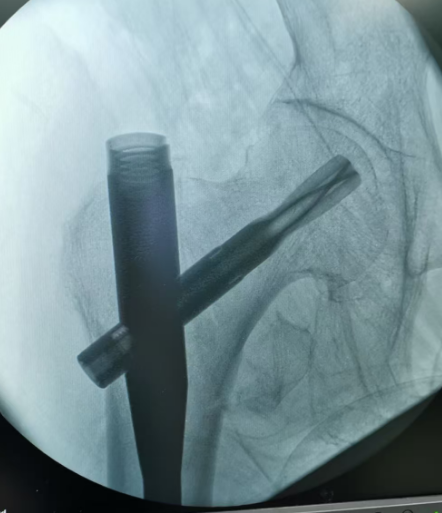

图:股骨转子间骨折手术固定